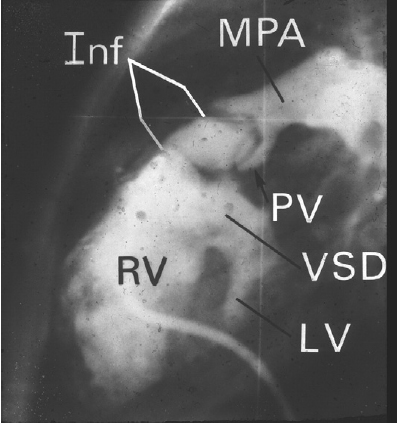

TOF 造影图片

1,肺动脉流出道梗阻(狭窄或者闭锁);

2,室间隔缺损;

3,主动脉骑跨;

4,右室肥厚。